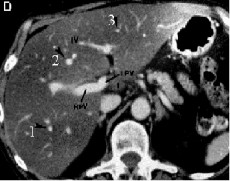

1.1.4. Phân chìa thùy và phân thùy gan trên CLVT:

Sự phân chia thuỳ và hạ phân thuỳ gan trên CLVT cũng dựa trên các mốc mạch máu đó là các tĩnh mạch gan và các nhánh phải và trái của tĩnh mạch cửa, các mặt phẳng tưởng tượng đi qua các mạch máu trên giúp phân biệt vị trí các thuỳ và phân thuỳ gan. Mặt phẳng qua TM gan phải chia gan phải thành phân thuỳ trước và sau. Mặt phẳng qua TM gan giữa chia gan thành gan phải và trái. Mặt phẳng qua TM gan trái chia gan trái thành thuỳ vuông và thuỳ đuôi. Mặt

phẳng ngang đi qua nhánh phải và trái phân chia các HPT trên gồm II, IVa, VII, VIII với các HPT dưới gồm III, IVb, V, VI [11].

Hình 1.4: Lớp cắt ngang qua nhánh trái và nhánh phải của TMC. Phía trên là HPT II, IVa, VII, VIII. Phía dưới các nhánh này là HPT III, IVb, V, VI [11].